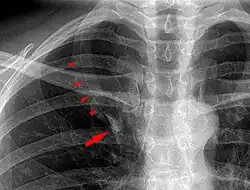

Azygos lobe

In human anatomy, an azygos lobe is a normal anatomical variation of the upper lobe of the right lung.[1] It is seen in 0.3% of the population.[2] Embryologically, it arises from an anomalous lateral course of the azygos vein,[3] in a pleural septum within the apical segment of the right upper lobe or in other words an azygos lobe is formed when the right posterior cardinal vein, one of the precursors of the azygos vein, fails to migrate over the apex of the lung and penetrates it instead, carrying along two pleural layers as the azygous fissure, that invaginates into the upper portion of the right upper lobe.[1]

An azygos lobe is usually an incidental finding on chest x-ray or CT scan. It is asymptomatic and not associated with any morbidity.[4][5] However, it can cause technical problems in thoracoscopic procedures.[6] The presence of the azygos lobe could alter the normal location of the superior vena cava or may be associated with other anomalies, including esophageal atresia or intrapulmonary right brachiocephalic veins.[7]